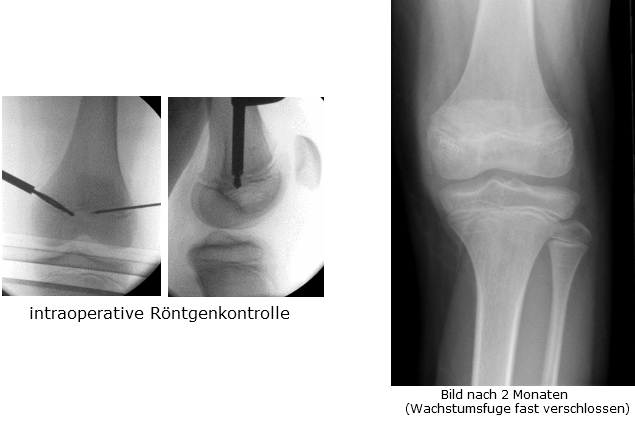

Bei Differenzen über 2 bis 3 Zentimetern sollten operative Therapien überlegt werden. Ist das Wachstumsende (Pubertät) noch nicht erreicht, kann mittels einer perkutanen Technik (minimale Technik über Stichinzision von ca 5 mm Länge) in Volnarkose die Wachstumsfuge des längeren Beines im Wachsen gestoppt werden. Der Patient hat danach kaum Schmerzen, muß für 3 Wochen mit Stützkrücken gehen und fällt für 6 Wochen vom Laufsport aus. Ansonsten bestehen keine Einschränkungen. Diese Operation erfolgt üblicherweise um das 11.bis 12. LJ bei Mädchen und das 13. LJ bei Knaben und erfordert eine noch offenen Wachstumsfuge. Nach Wachstumsabschluß ist diese Methode daher nicht mehr zielführend.